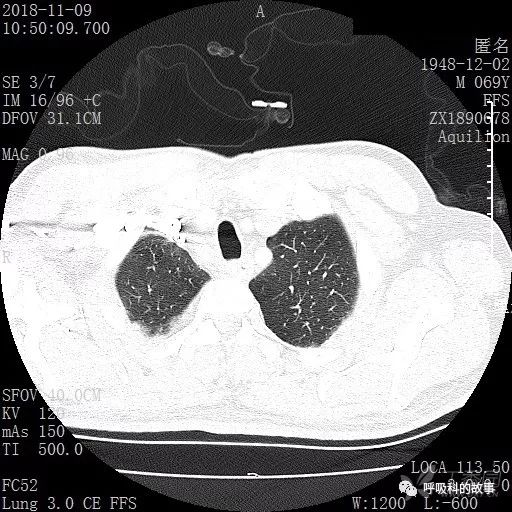

胸部增强CT示右肺门占位伴远端阻塞性肺炎,纵膈、右肺门、右侧颈根部、右侧腋下及肝门部肿大淋巴结。两侧胸腔少量积液。

肺窗CT